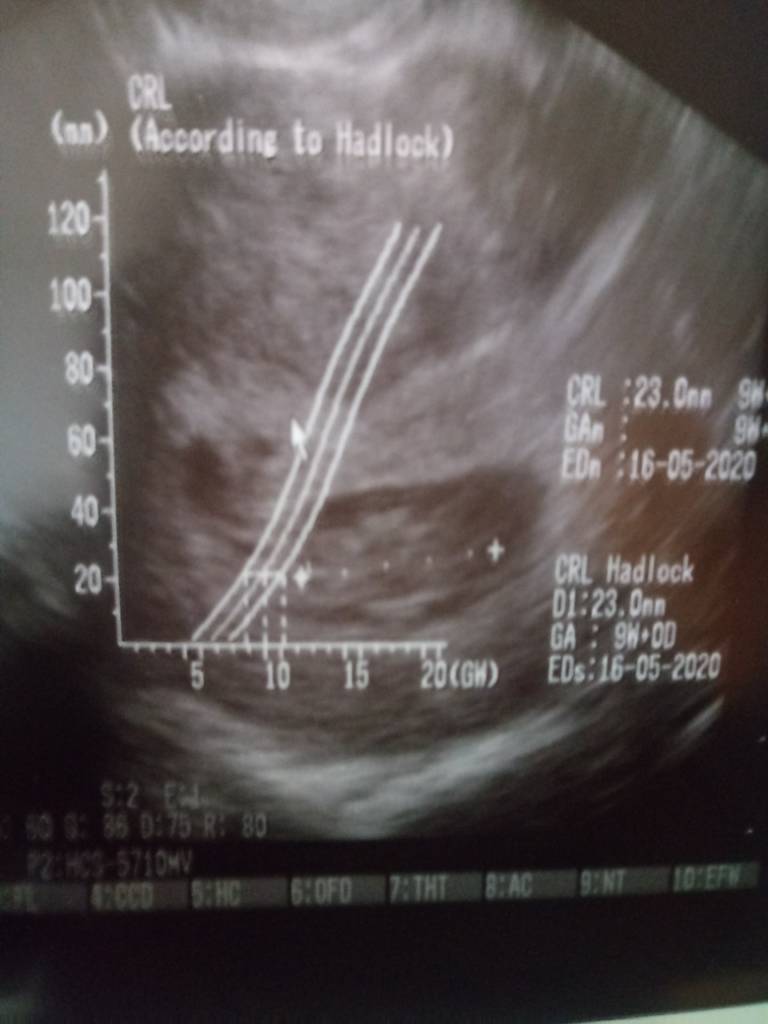

ja dziewczynki nadal leżę, bylam dzisiaj u gina zobaczyć czy wszystko jest ok, czy serduszko bije i jak tam jest z tym moim krwiakiem. Więc z dzidzią jest wszystko ok, serduszko bije, dzisiaj jest moj 9t1d a dzidzia ma 23mm, tydz temu bylo 11 mm wiec prawidlowo rośnie. A krwiak tydz temu miał prawie 2 cm teraz jest 9mm wiec sie zmniejsza. Dzięki Bogu! Lekarz powiedział, że będę jeszcze przez jakis czas plamic na brązowo bo krwiak sie musi oczyścić. Niby nie kazał mi leżeć caly czas tylko sie oszczędzać ale poleże jeszcze na wszelki wypadek. Nastepna wizyta za 2 tyg. Kamień spadł mi z serca bo bałam sie o serduszko...ale maluszek jest silny. Powodzenia dla was kochane.

ja dziewczynki nadal leżę, bylam dzisiaj u gina zobaczyć czy wszystko jest ok, czy serduszko bije i jak tam jest z tym moim krwiakiem. Więc z dzidzią jest wszystko ok, serduszko bije, dzisiaj jest moj 9t1d a dzidzia ma 23mm, tydz temu bylo 11 mm wiec prawidlowo rośnie. A krwiak tydz temu miał prawie 2 cm teraz jest 9mm wiec sie zmniejsza. Dzięki Bogu! Lekarz powiedział, że będę jeszcze przez jakis czas plamic na brązowo bo krwiak sie musi oczyścić. Niby nie kazał mi leżeć caly czas tylko sie oszczędzać ale poleże jeszcze na wszelki wypadek. Nastepna wizyta za 2 tyg. Kamień spadł mi z serca bo bałam sie o serduszko...ale maluszek jest silny. Powodzenia dla was kochane.Zobacz załącznik 1033025